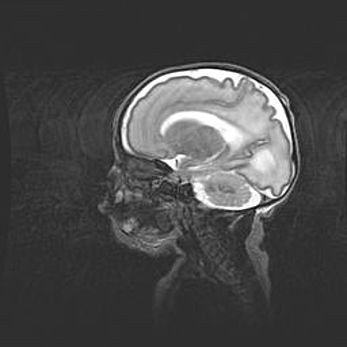

Мальформация Денди-Уокера. Киста задней черепной ямки.

Агенезия мозолистого тела.

Возраст: 2,5 месяца

Вес: 2420 г

Пол: женский

Окружность головы: 37 см

Срок гестации: 32 недели

Мальформация Денди—Уокера — редкий вид патологии ЦНС, представляющий собой врожденный порок развития каудального отдела ствола и червя мозжечка, ведущий к неполному раскрытию срединной (Мажанди) и латеральных (Лушка) апертур IV желудочка мозга. Для этогно синдрома характерна триада симптомов: гипотрофия червя мозжечка и/или полушарий мозжечка, кисты задней черепной ямки, гидроцефалия различной степени. В 70% случаев порок сочетается и с другими аномалиями головного мозга, в частности с агенезией мозолистого тела.